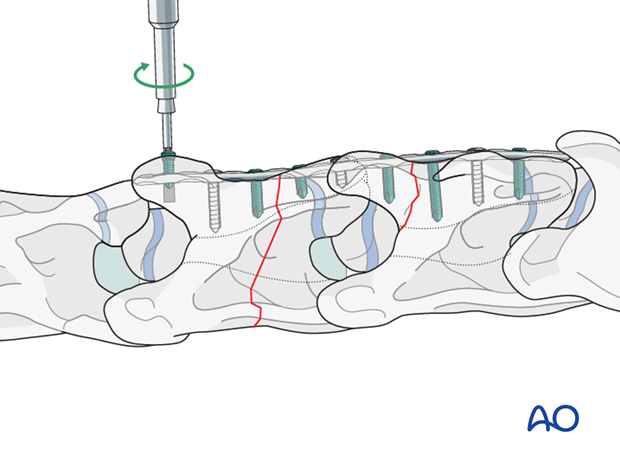

Intraoperative radiographic control of the drilling depth and screw positioning is critical to prevent penetration of the vertebral canal.

The image shows intraoperative radiographic control of the drilling depth and screw positioning.

Note: Penetration of the spinal canal with the drill must be avoided.